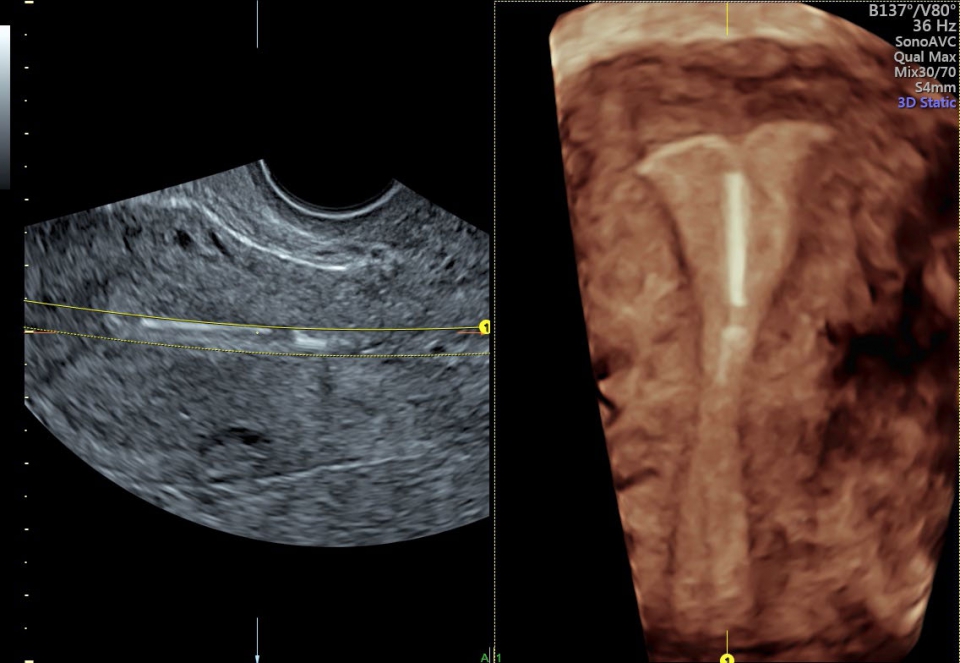

• SonoAVC (Автоматический расчет объема): Эта функция позволяет визуализировать и рассчитывать размеры и объем гипоэхогенных образований, таких как фолликулы яичника или структуры головного мозга плода. Она помогает в оценке этих образований и отслеживании их изменений в течение времени.

SonoAVC:

Да